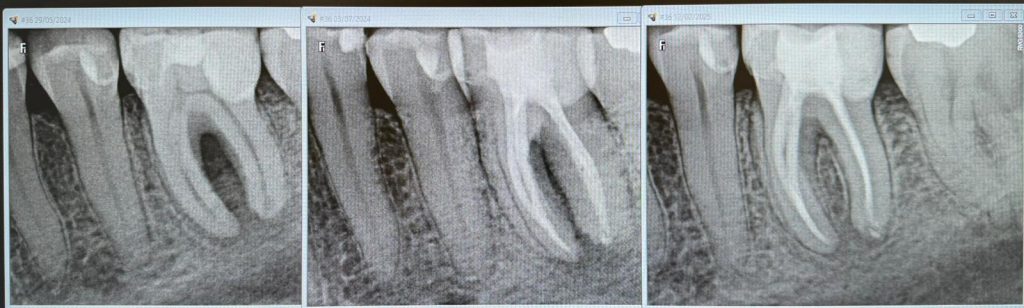

Tratament Endodontic Smiledent – Inainte și După

Tratamentul de canal constă în eliminarea nervului din canalele rădăcinilor, urmat de obturarea acestora cu material care asigură sigilarea și împiedică infecția. Acest tratament are ca scop inițial, îndepărtarea durerii și prevenirea infecției, însă scopul final este menținerea functionalității dintelui.